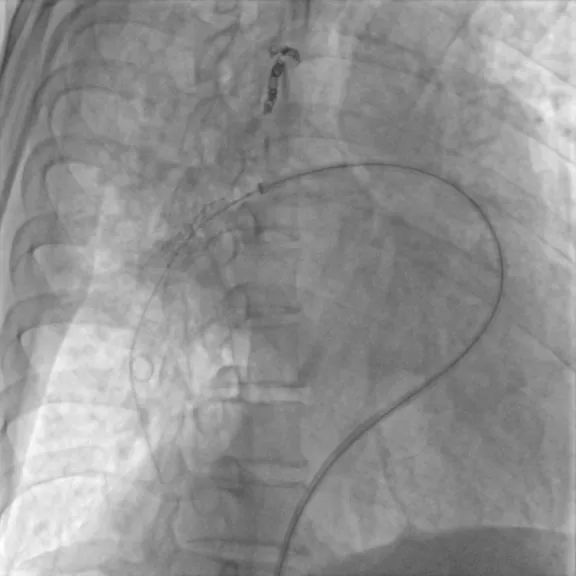

第四次(2021.7)拟行肺动脉支架植入术入院,于2021-7-7行右心导管检查+肺动脉造影+肺动脉支架植入术:支架植入前测量右房压为25/9(15)mmHg,右心室压为55/2(19)mmHg,肺动脉压为55/29(38)mmHg,CO 2.2 L/min,PVR 11.8WU。测量左肺下叶肺动脉近端压力51/23(32)mmHg,远端压力为15/11(12)mmHg,右肺下叶肺动脉近端压力52/20(31)mmHg,远端压力为11/8(9)mmHg,于右肺动脉基底干狭窄处植入PLU-STENT M30支架一枚,测量病变远端压力为51/23(32)mmHg,未见明显压差。

术前肺动脉造影

肺动脉支架植入术